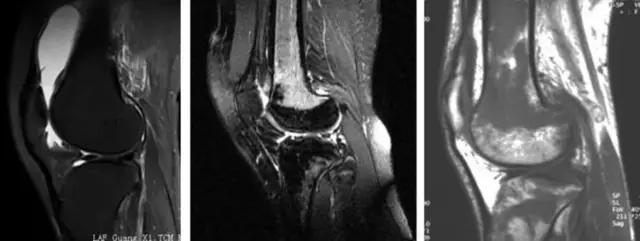

地中海贫血与白血病均为血液系统的问题,主要表现在骨髓,疾病的发病机理有别,MRI表现也不相同;我们可能不是很熟悉这些疾病,也能够从MRI发现区别。图1:正常膝关节 图2:地中海贫血 图3:白血病